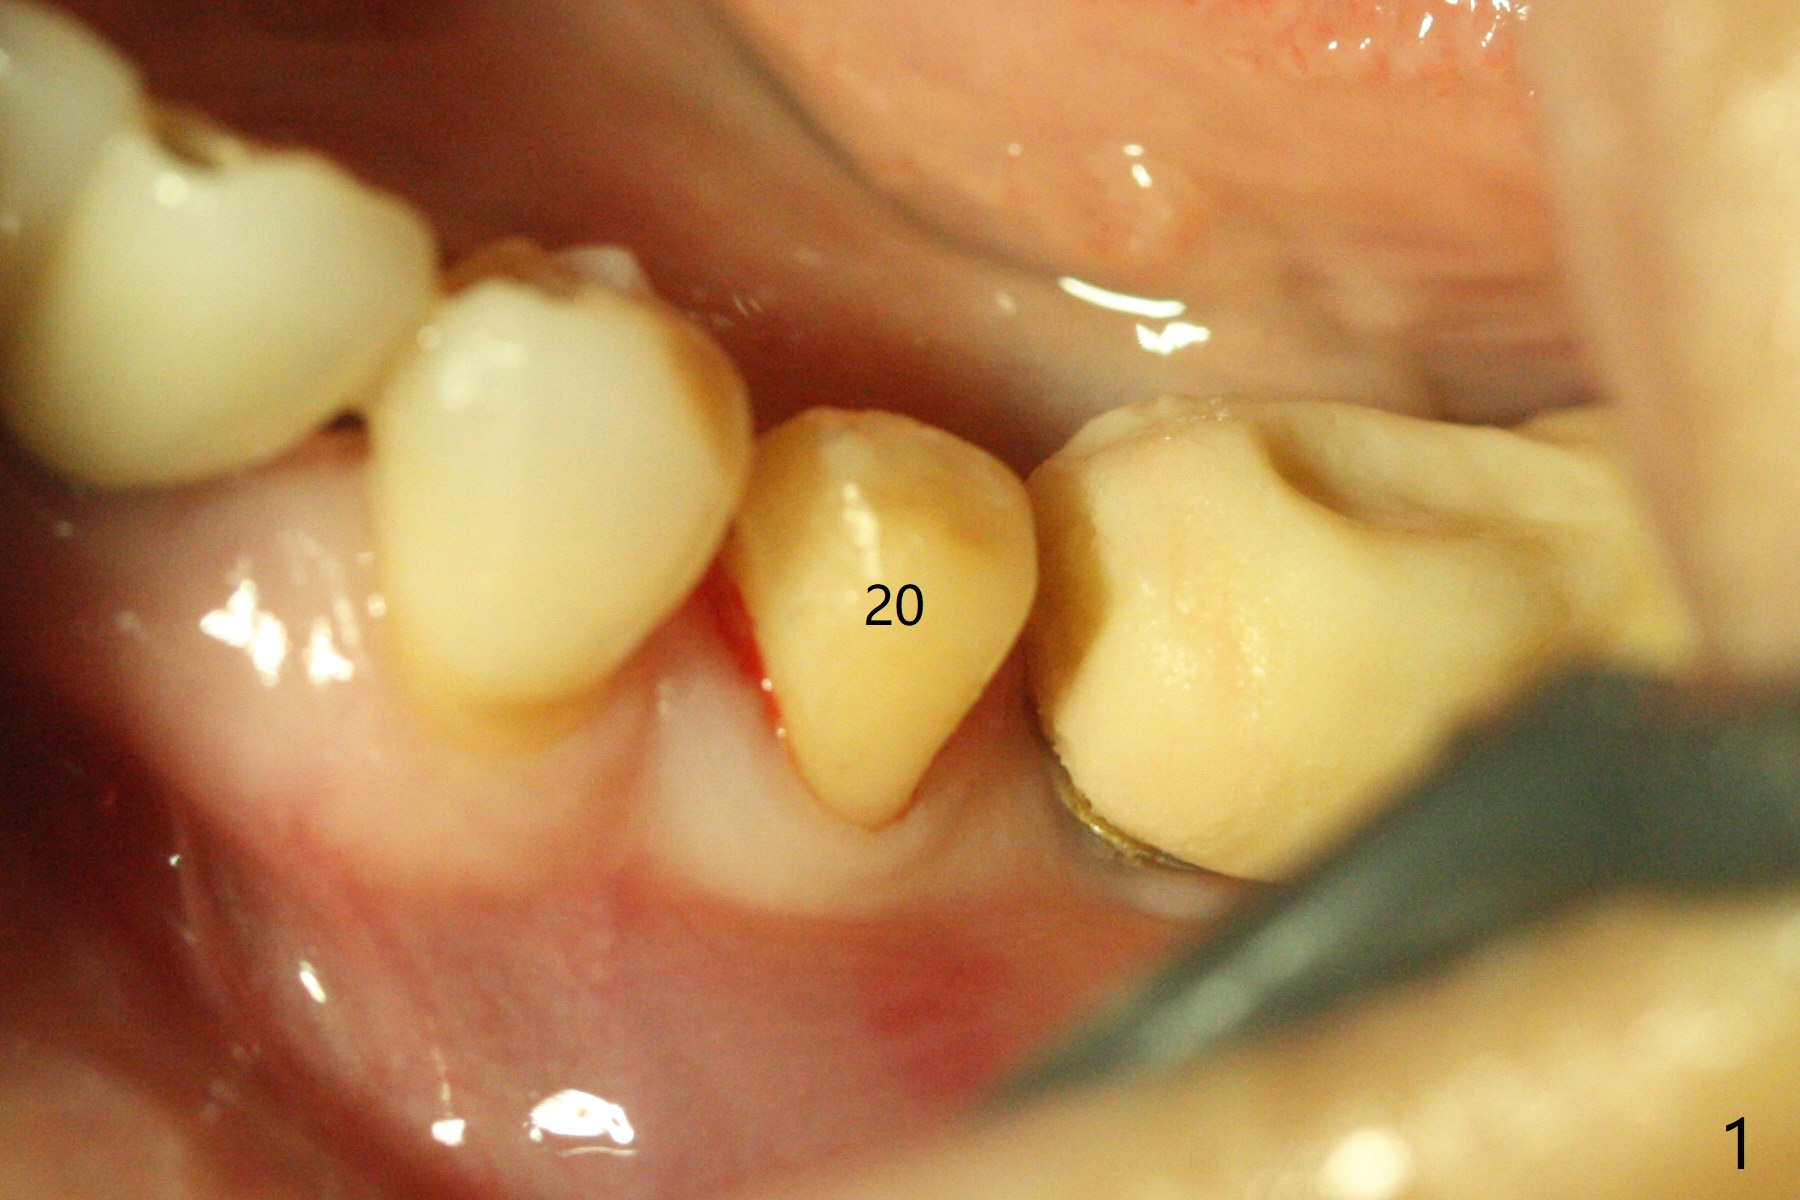

Socket Shield is conducted at #20 (Fig.1-3 *). With placement of a 4x11.5 mm implant equicrestal lingually, a 4.5x6(2) mm temporary abutment is unable to be seated incompletely (Fig.4 black <) because of proximal crestal interference (white arrowheads). After use of a 5.5 mm profile drill, a 5.5x5 mm healing abutment is apparently seated completely (Fig.5). Upon close look, the abutment at #19 is also incompletely seated. In fact #18/19 temporary crowns and #19 abutment are loose. A 6.8x4 mm healing abutment is later placed at #19. Periodontal dressing is applied at #18-20. In fact buccolingual control of osteotomy is not easy with free hand. A smaller implant (e.g., 3.5 mm) may be easier.